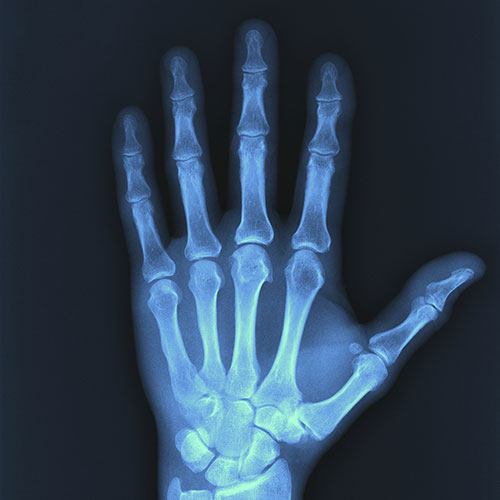

Un examen de rayos X crea imágenes de sus órganos internos o huesos para ayudar a diagnosticar condiciones o lesiones. Una máquina especial emite (apaga) una pequeña cantidad de radiación ionizante. Esta radiación atraviesa su cuerpo y se captura en un dispositivo especial para producir la imagen.

La dosis de radiación que recibirá depende del área de su cuerpo que se esté examinando. Las áreas más pequeñas, como la mano, reciben una dosis menor en comparación con un área más grande, como la columna vertebral. En promedio, la dosis de radiación es aproximadamente la misma que recibiría del entorno general en aproximadamente una semana.

El calcio en los huesos bloquea el paso de la radiación, por lo que los huesos sanos se ven blancos o grises. Por otro lado, la radiación pasa fácilmente a través de los espacios de aire, por lo que los pulmones sanos se ven negros. Cuando se utilizan exámenes de rayos X Esta prueba es muy común. Cada año se realizan alrededor de siete millones de exámenes de rayos X en Australia. Algunos de los muchos usos incluyen:

– Un simple examen de rayos X convencional, de la mano, por ejemplo, suele tardar unos minutos. Otros tipos de exámenes de rayos X pueden tomar más tiempo. Inmediatamente después de una radiografía Después de la radiografía, puede vestirse (si se cambió de ropa) y esperar más instrucciones. Un radiólogo interpretará las imágenes de rayos X. Los resultados generalmente se envían a su médico, por lo que deberá programar una cita de seguimiento. Complicaciones de los exámenes de rayos X. Un examen de rayos X es un procedimiento indoloro y no invasivo. No será radiactivo después de la prueba. La dosis de radiación se considera segura, aproximadamente la misma que recibiría del entorno general en aproximadamente una semana.